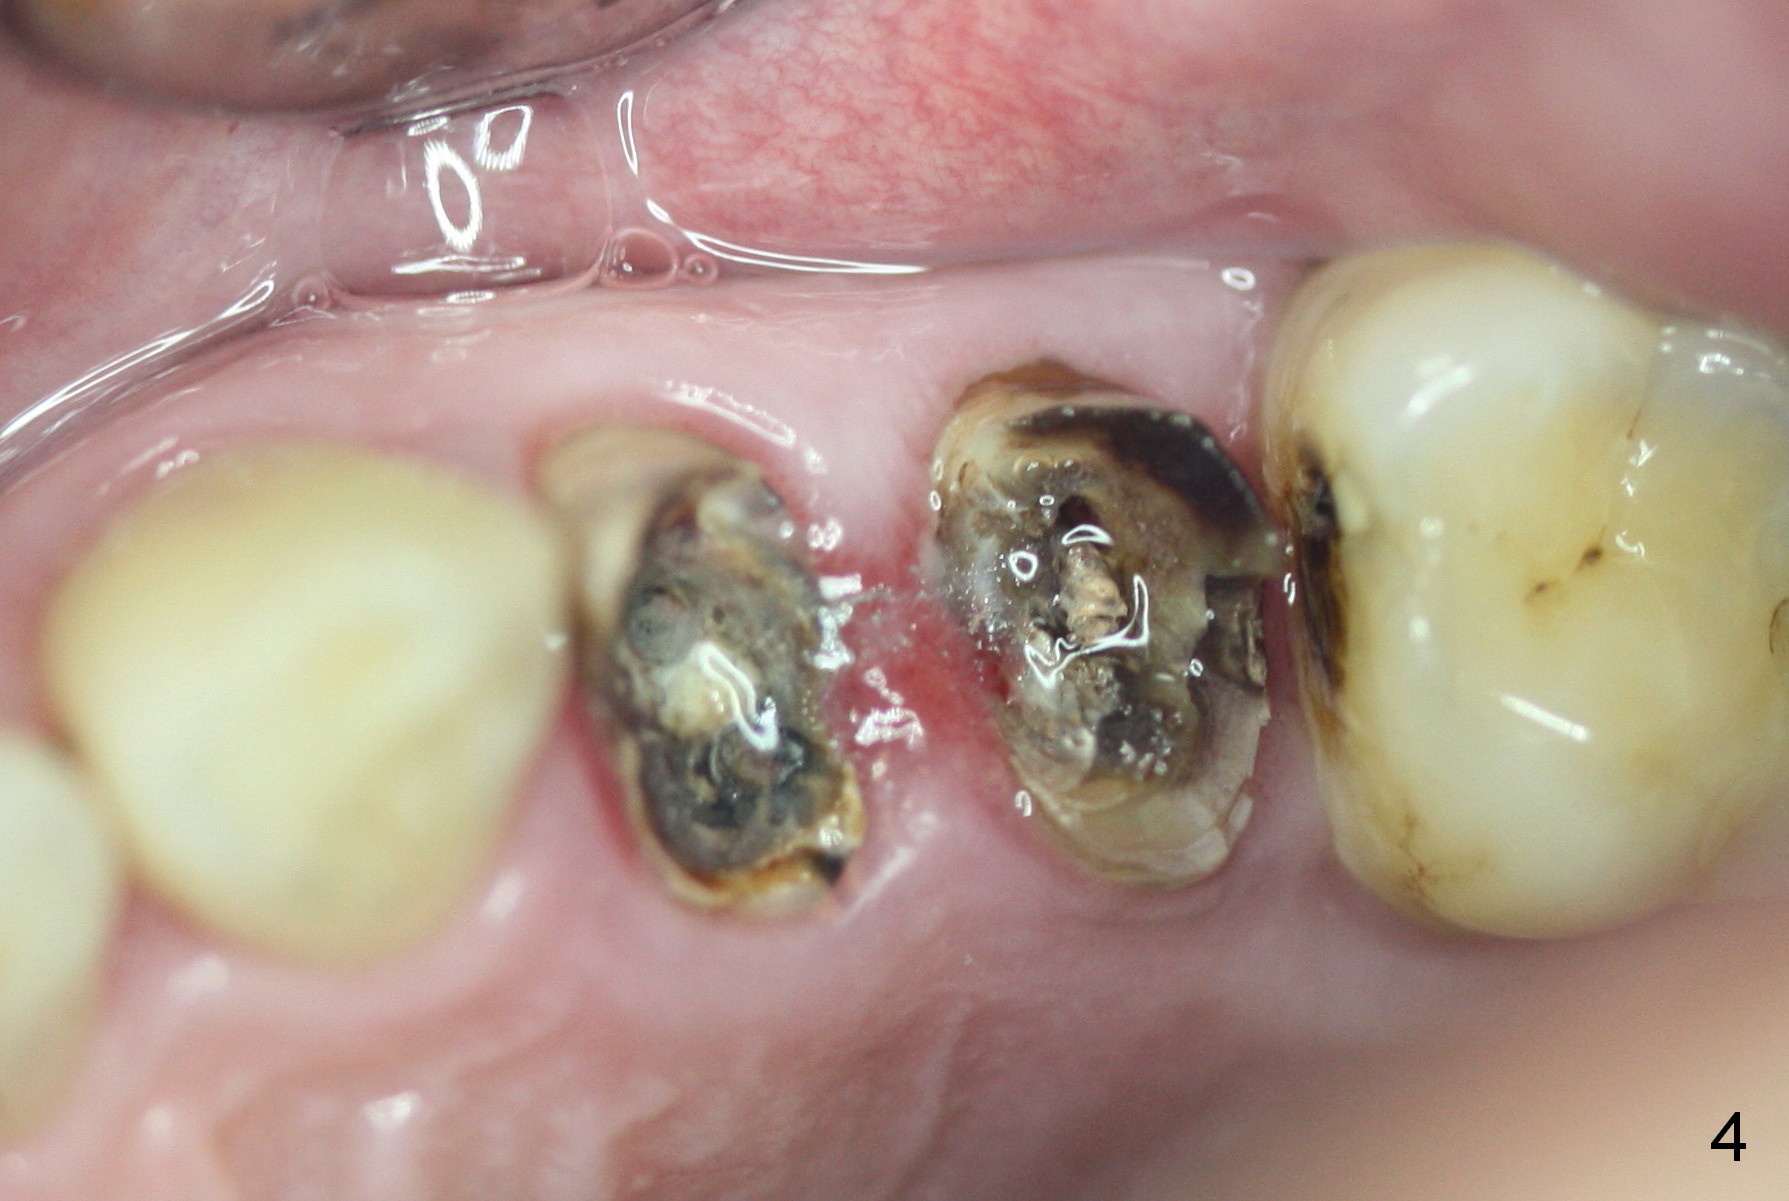

A 45-year-old man presented to our office 8 years ago (Fig.1,2) and got work done somewhere else. He returned yesterday with chief complaint "I might swallow my crowns". Exam shows residual roots at #12,13 (Fig.3,4). The patient has strong jaw bone, suggesting that the bone density is high. Either bone- (Fig.5) or tissue- (Fig.6) level implants will be placed. By time sequence, this case will be assigned to the control group of the antibiotic study. Preop PA does not catch the apices (Fig.3). Take a new one with sensor 1 prior to surgery or panoramus.